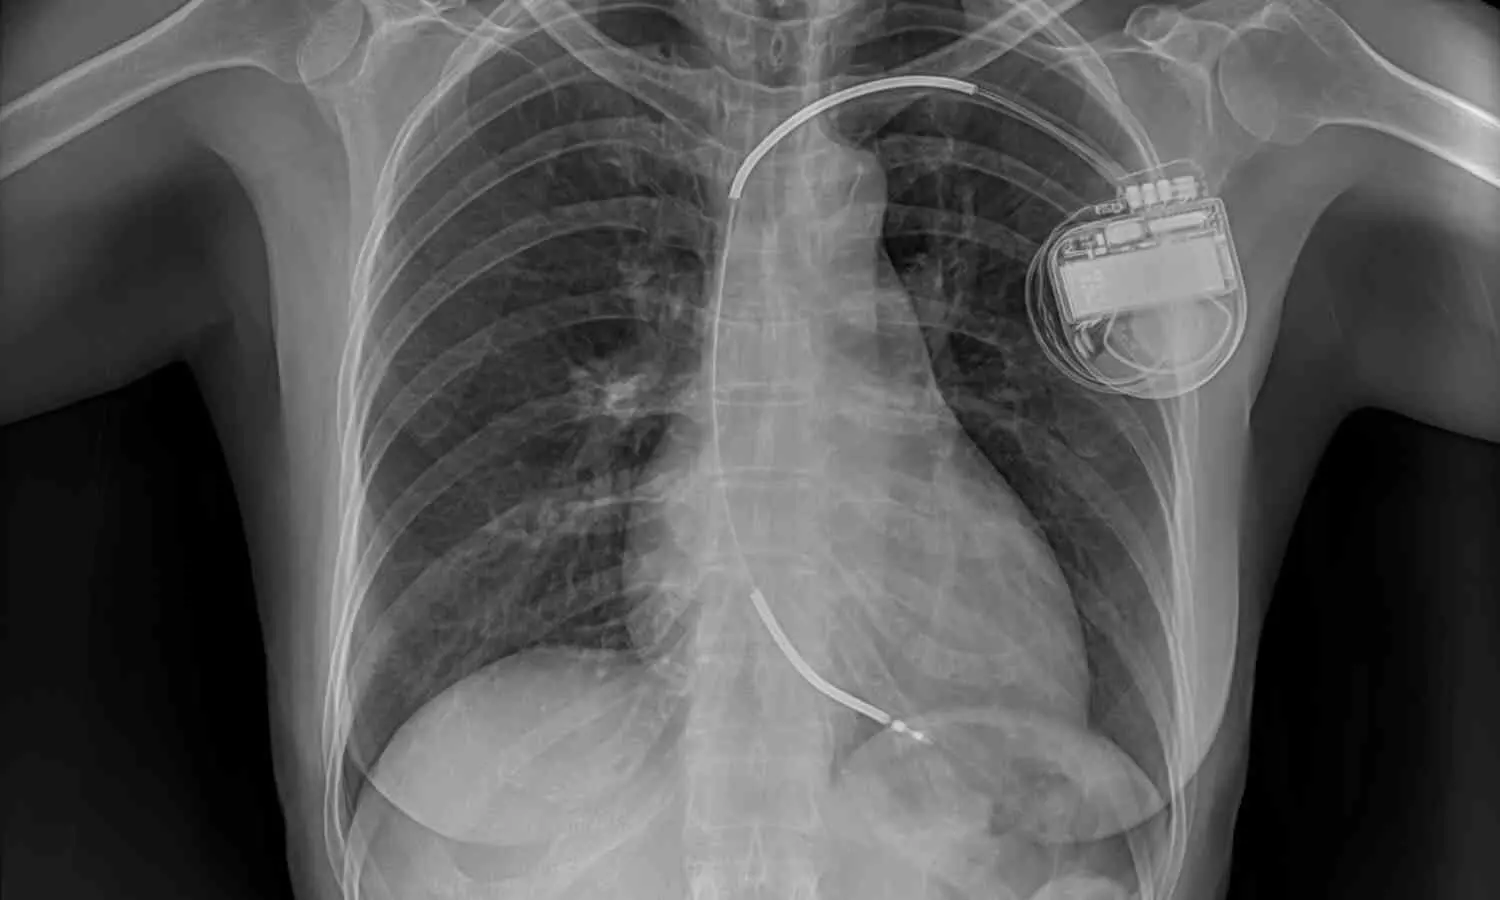

Researchers from Beijing Chao-Yang Hospital detail the case of a 60-year-old woman with a decade-long history of exertional dyspnea and chest tightness after occupational exposure to iron dust. Imaging revealed pulmonary hypertension and right middle lobe atelectasis due to mediastinal compression. After biopsy confirmed fibrosing mediastinitis, the care team administered two courses of rituximab injections into hypermetabolic lymph nodes under endoscopic ultrasound guidance.

Two months after the second injection, CT scans showed resolution of atelectasis, PET-CT demonstrated reduced metabolic activity, and the patient’s 6-minute walk distance improved from 0 to 230 meters. Subsequently, balloon angioplasty of severely stenotic pulmonary arteries further improved hemodynamics, reducing mean pulmonary artery pressure and increasing walk distance. Lung function also improved significantly. The only adverse event was influenza, managed successfully. To the author’s knowledge, this is the first reported case of lymph node–targeted rituximab for fibrosing mediastinitis. The authors note that further studies are needed to confirm safety and efficacy of this novel approach.